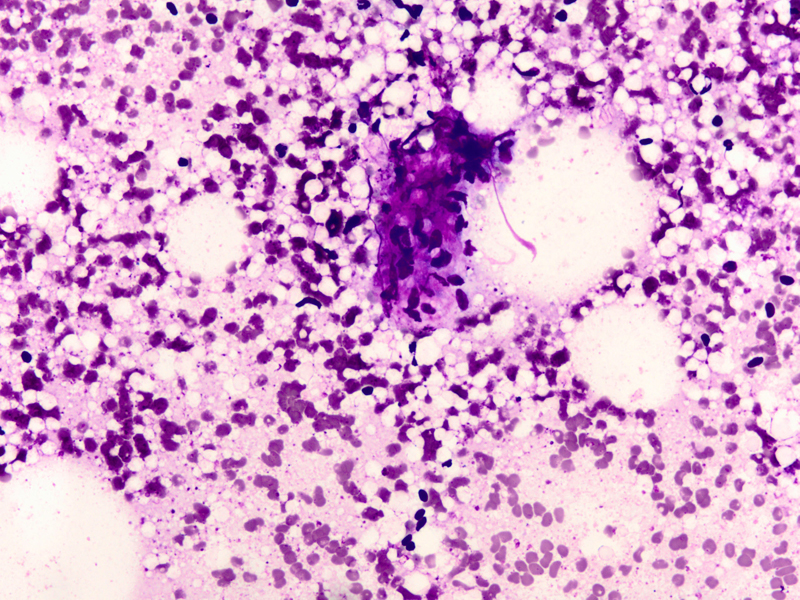

• Fig 3: FNA cytology, Diff-quik stain, X400

Cytologic findings

• Moderately cellular smear

• Branching clusters of ductal epithelial cells, dissociated single cells, or rarely acinar or papillary arrangements

• Polygonal to round ductal epithelial cells with uniform nuclei, abundant cytoplasm and inconspicuous nucleoli

• Focal marked atypia may be seen in benign adenomyoepitheliomas (1).

• Abundant myoepithelial cells as round to spindled shaped cells, as bare oval nuclei in the background or overlying epithelial cell clusters, or as cells with clear cytoplasm

• Focal aggregates of spindled cells

• Fragments of myxoid or fibrous stroma

• Intranuclear inclusions (1) and intracytoplasmic vacuoles (2) have been described

• Thin proteinaceous debris, histiocytes and apocrine cells may be seen

Discussion: Adenomyoepithelioma was first reported by Hamperl in 1970 as an uncommon biphasic tumor composed of epithelial and myoepithelial cells (3). Adenomyoepitheliomas usually present as a single circumscribed mammary nodule. The fine needle aspiration findings in adenomyoepitheliomas have been described in only a few reports (1, 2, 4-11). It is important to recognize this entity as the radiologic and cytologic features can mimic malignancy. On cytology single enlarged atypical epithelial cells, presumed to be of myoepithelial origin due to staining with S-100 protein have been noted and led to the erroneous diagnosis of carcinoma (6). Only rarely can this diagnosis be made definitively on fine-needle aspiration biopsy (7). Histologic patterns include the tubular, lobulated and spindle cell variants (12). Biphasic pattern consists of tubules lined by cuboidal or columnar shaped epithelial cells surrounded by myoepithelial cell layer, Malignant adenomyoepitheliomas are usually characterized by cellular pleomorphism, necrosis, high mitotic activity and invasion of the surrounding tissue. Immunohistochemistry illustrates the biphasic nature of adenomyoepitheliomas with staining for low molecular weight cytokeratin and epithelial membrane antigen in the epithelial component and staining for smooth muscle actin, S-100 protein, calponin, p63 and maspin in the myoepithelial cell component (8)